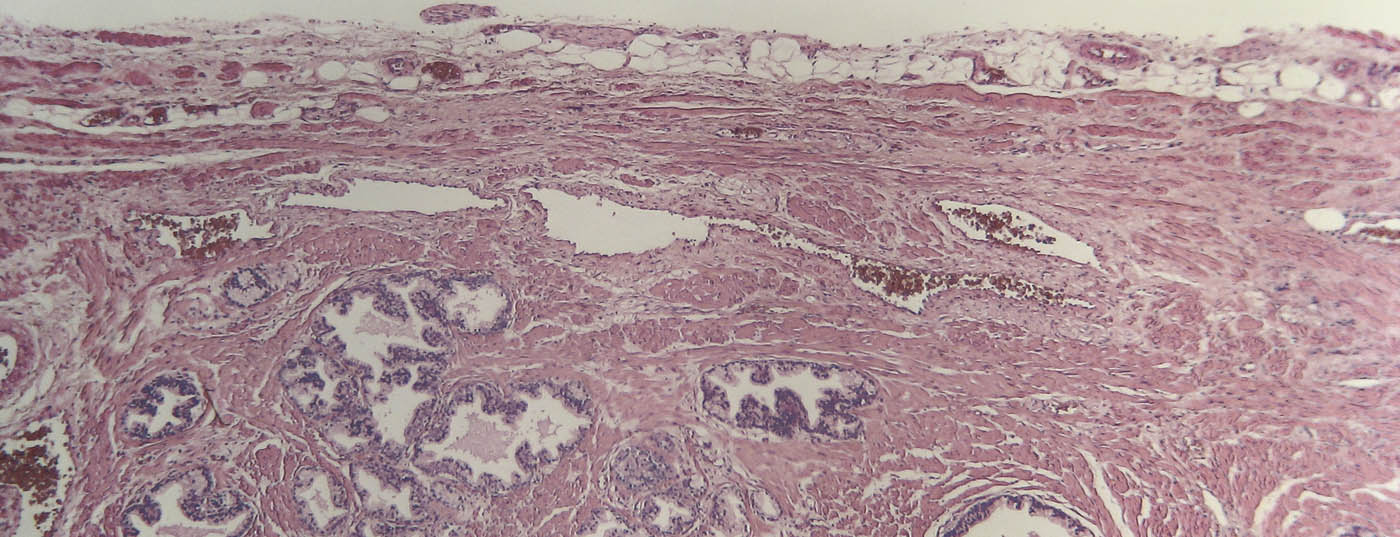

prostata_histo

• Multiparametrische MRT beim Prostatakarzinom

Ein Mittel, um die diagnostische Exaktheit zu erhöhen

Lässt sich die multiparametrische MRT in der Triage nutzen, um bei einem Teil der Betroffenen un­nötige Prostata-Biopsien zu vermeiden und beim anderen in der ­Biopsie gezielter vorzugehen? ­Gemäss den ­Resultaten einer ­britischen Studie aus dem Lancet lautet die Antwort «Ja». Die Autoren sehen verschiedene Vorteile einer solchen Vorauswahl.